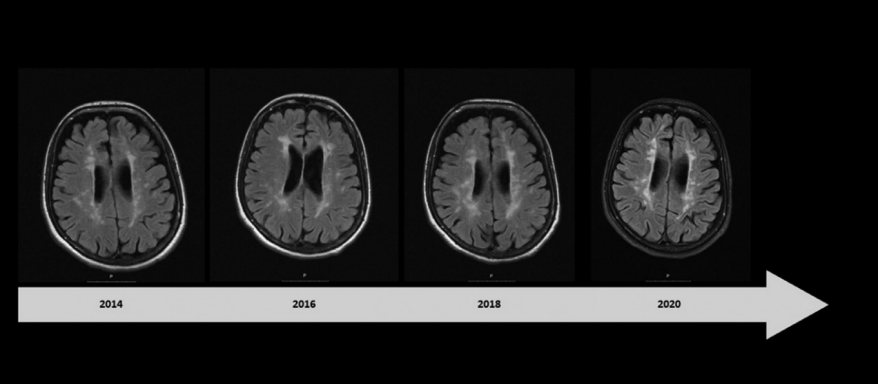

2018年,患者出现了进行性加重的延髓受累表现,如构音障碍、吞咽困难等。但反复的神经影像学评估未发现明确的MS病变(图2),因此诊断为继发性进展性MS。2020年5月,患者开始使用奥克雷珠单抗,到2021年6月患者的上、下肢无力症状又有加重(EDSS 6.0),遂来我院就医(病情发展和治疗示意见图3)。

图2 脑和脊髓MRI。矢状位的T2-FLAIR扫描显示胼胝体萎缩(图A,绿色区域),未发现新的脑干病变(A,箭头);病变主要影响脑室周围白质(Dawson指)(图B,虚线箭头);矢状面T2加权扫描排除了颈椎束中有新的脱髓鞘病变发生(图C)。 图3 疾病发展和诊断治疗的时间线:EDSS:扩展的伤残状态量表。IFN-β:β干扰素。TFN: 特利氟米特。FNG: 芬戈利莫德。OCR: 奥克雷珠单抗。 入院时,她面容憔悴,肢体无力,只能通过平板电脑进行交流,且有蹒跚步态、咳嗽无力、反式呼吸、严重流涎、情绪不稳定的表现。体格检查发现:患者舌肌萎缩、颈部肌肉和上下肢肌肉均无力且萎缩明显,下肢还有肌痉挛表现。肌力评估:右上肢瘫痪,MRC2级,左上肢MRC3级,下肢为4级。患者深感觉、浅感觉均正常,四肢腱反射尚灵敏(3+),足底反射为屈曲。 检测患者的视觉诱发电位发现,其视神经可能存在双侧基底节前神经传导障碍,而其听觉和体感诱发电位检测未提示异常。周围神经传导无异常,针极肌电图显示运动单元明显减少,舌肌有神经再形成的迹象,慢性神经源性运动单位的电位较高。双上肢和下肢近端和远端肌肉出现急性去神经化的表现,如肌肉颤动和肌电尖波。 在对患者做了NGS测序(包括运动神经元疾病相关的的119个基因,其中82个为核基因,37个为线粒体基因),并结合DNA的半定量分析、聚合酶链反应(PCR)、实时qPCR和多重结扎依赖探针扩增(MLPA)后发现:C9orf72基因扩增阴性,但位于15q21.1上SPG11基因的两个意义不明(VUS)杂合变异通过了筛选:SPG11 (NM_025137.3) c.4669G>A(p.(Glu1557Lys))和SPG11(NM_025137.3)c.6877C>T(p.(Arg2293Trp))。前者为内含子变异,后者为错义变异,结果预测为功能丧失可能。且这两种变异在ALS 5型、痉挛性截瘫11型(SPG11)和CMT2X(Charcot-Marie-Tooth disease type 2X)的患者中都有被报道过。 综上,患者被诊断为ALS,并开始用利鲁唑治疗,后又开始用无创通气辅助呼吸,经皮内窥镜胃造口术进食等。此后,患者在家里接受物理和药物治疗,然而病情仍在不断恶化,最终于2022年5月去世。 讨论 DMT疗法显著延长了MS患者的生存期,但也为之带来了更高的罹患衰老相关的神经退行性病的风险。MS患者的肌肉萎缩,或是因为皮质脊髓束功能障碍、不活动和肌肉失用共同所致。然而,也有一些研究证实MS和ALS之间确有联系。已知C9orf72基因的重复扩增可导致脑白质脱髓鞘病变,而少数ALS患者的C9orf72基因也有六核苷酸重复扩增。一个包含了650名ALS患者入组的队列研究发现,有5名ALS患者同时患有MS(其中4位有C9orf72基因核苷酸重复扩增)。与我们的这例患者类似,文献报道的病例大都在确诊ALS之前被诊断为MS,且其中大多数是RRMS—这显然是因为MS起病年龄较小。多数患者始于肢体肌肉萎缩和肌无力,只有少数病例有横纹肌病变症状。 本病例或证明了一个不幸的巧合,或又是MS和ALS之间联系的一个例证。MS被公认为是一种神经炎性病,而ALS则被认为是一种神经退行性病。但越来越多的证据表明,ALS的神经退行性标志物如线粒体功能障碍、氧化应激和细胞骨架蛋白代谢障碍也与MS患者的病情进展有关。同时,本病例的遗传学检测结果提示SPG11的致病可能性。已有研究表明,SPG11基因敲除小鼠出现了早发性运动功能障碍和认知异常,与ALS模型动物的表型相似。从临床表现上来说,两者都会出现四肢瘫;从神经病理学上来讲,蛋白泛素化异常、p62聚集和运动神经元变性也是ALS的标志;而且SPG11基因变异也被认为是青少年ALS的遗传因素之一。SPG11基因编码spatacsin,命名源自“痉挛伴胼胝体变薄或萎缩症蛋白”,虽然生信报告提示该突变是VUS,但这一发现或会激发对SPG11表型及它与MS关系的讨论,虽然目前二者的关联并不那么直接。